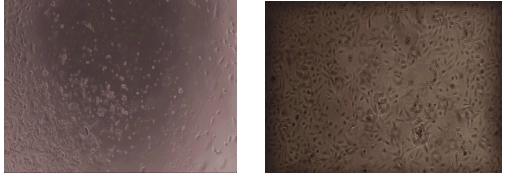

| Bio-activity : | TNF-β, a member of the tumor necrosis factor family, is a potent lymphoid factor that exerts cytotoxic effects on a wide range of tumor cells. The biological effects of TNF-β are very similar to TNF-α, due to the similarity of molecular structure and the receptors. As reported, TNF-β could inhibit the proliferation and induce necrosis of A549 cells, and the concentration of IL-1β in cell supernatant will increase after stimulation. Therefore, A549 cells were incubated in DMEM with TNF-β (10ng/mL) for 8h, 24h, 48h, 72h, then cells were observed by inverted microscope and IL-1β was detected in the cell supernatant by ELISA . |